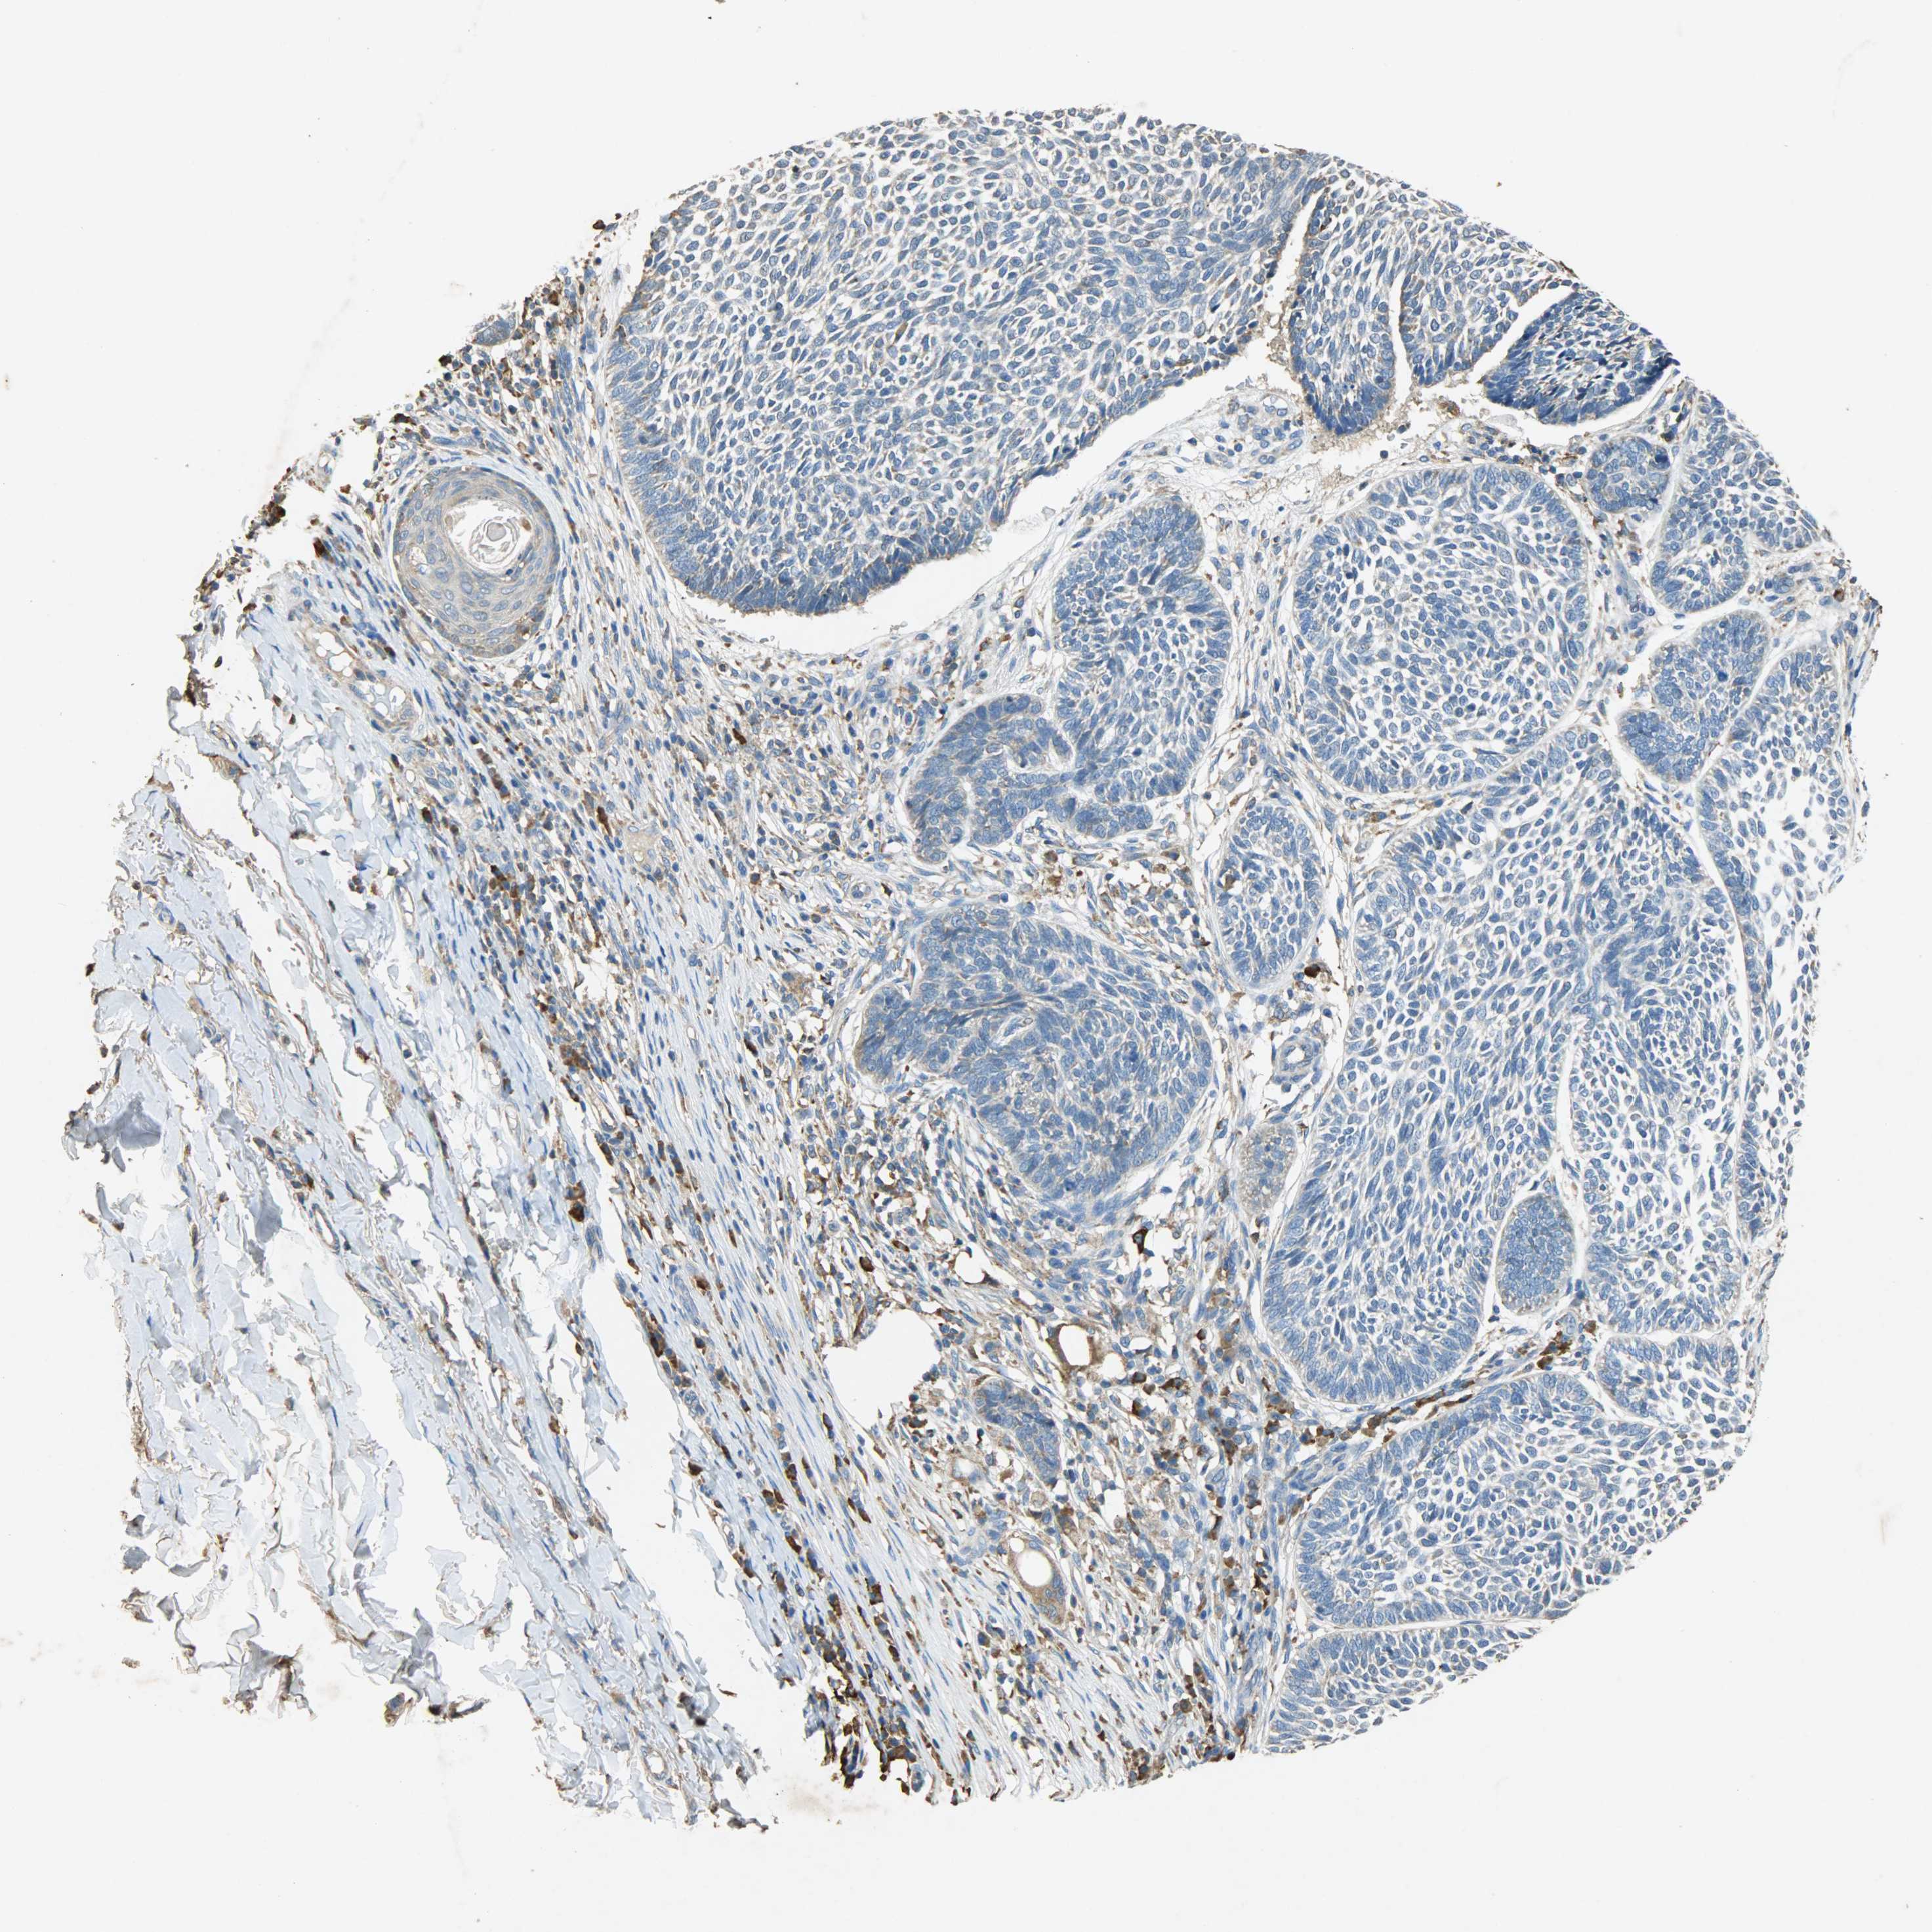

Antibody HPA038846

Squamous cell carcinoma, NOS